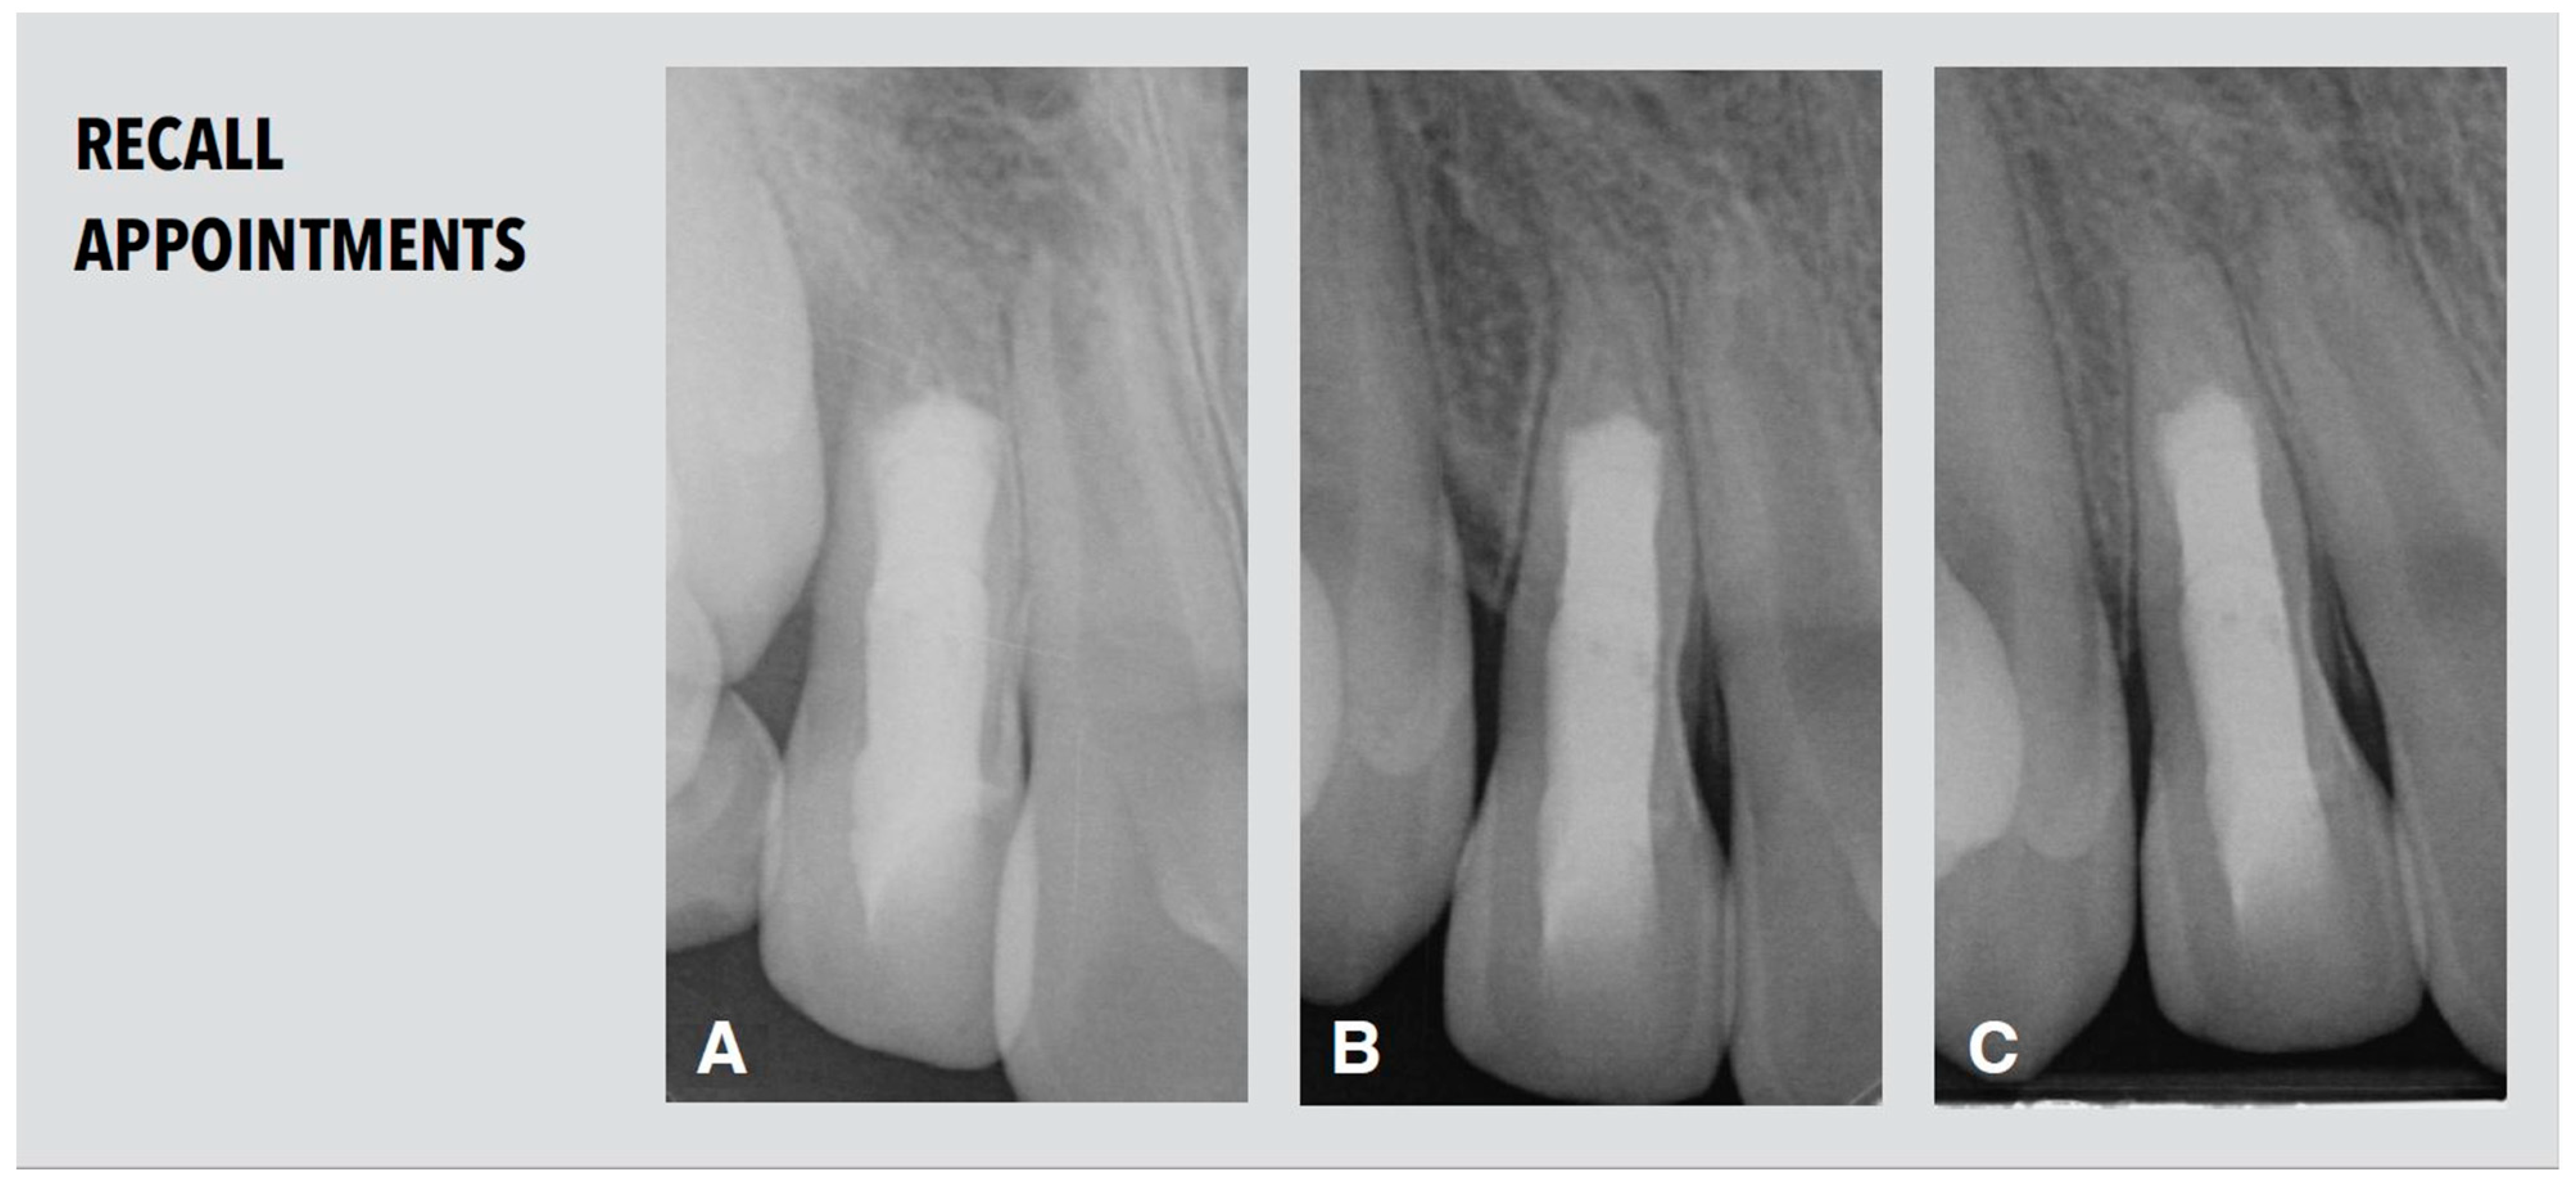

2.5. Recall Appointments